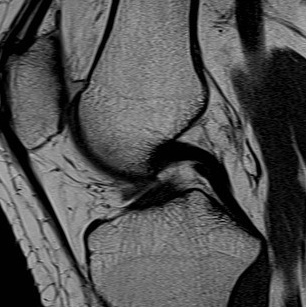

MRI

PCL completely torn

PCL midsubstance tear with lengthening

PCL tibial avulsion

PCL femoral avulsion